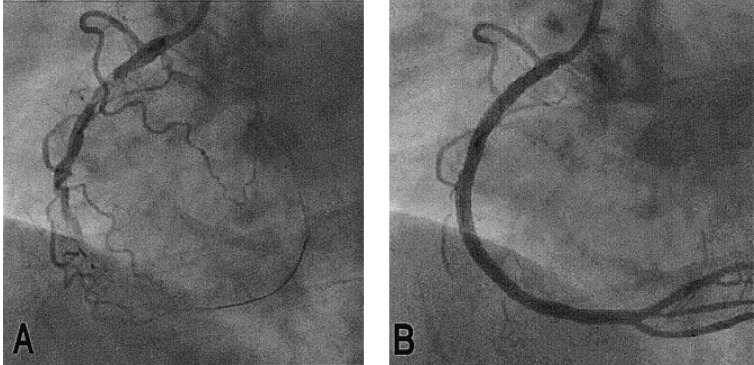

Figure 2

Coronary angiogram. (A) Total occlusion of the mid RCA and 70% narrowing of proximal RCA is shown. (B) After successful coronary angioplasty with stents at the proximal RCA and mid RCA, the occlusion was recanalized.